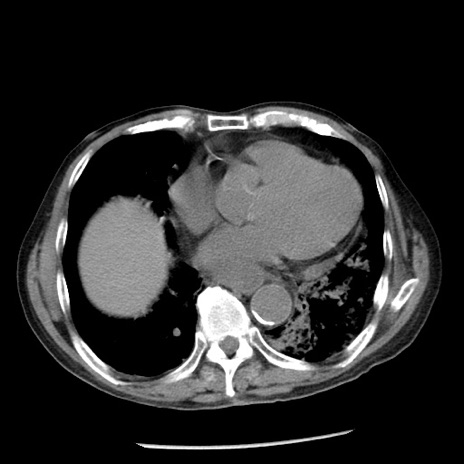

症例26(横断像)

冠状断像

【症例】80歳代男性

【主訴】嘔吐

【現病歴】昨晩2回嘔吐あり、今朝になっても嘔吐あり。来院。

【既往歴】胃潰瘍

【身体所見】意識清明、BT 37.6℃、BP 166/95mmHg、HR 100bpm、SpO2 97%、腹部:平坦・軟、腸蠕動音聴取良好、圧痛なし。

【データ】WBC 21900、CRP 1.46